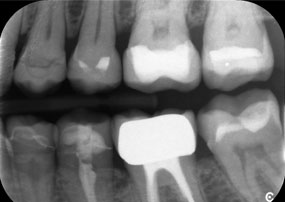

Ein weiteres Beispiel für die klinische Leistungsfähigkeit der Power Edition war der Austausch einer beschädigten Zirkonkrone bei einer 63-jährigen Patientin. Diese stellte sich aufgrund eines abgesplitterten Verblendungsteils ihrer 20 Jahre alten Zirkonkrone an Zahn 6 vor. Trotz der Position im Seitenzahnbereich empfand die Patientin dies als störend und wünschte eine neue Krone.

Die Power Edition ermöglichte eine präzise Schnittführung, wobei das erhöhte Drehmoment und die verbesserte Kühlung dazu beigetragen haben, die Krone ohne größeren Materialverlust zu entfernen. Das Spannsystem und das verbesserte Drehmoment erwiesen sich hierbei als essenziell.

Ein Röntgenbild, das Zähne und eine Zirkonkrone zeigt, vor schwarzem Hintergrund.

Abbildung 2: Austausch einer beschädigten Zirkonkrone: Präzise Erneuerung einer beschädigten Zirkonkrone an Zahn 6 mit minimalem Materialverlust.